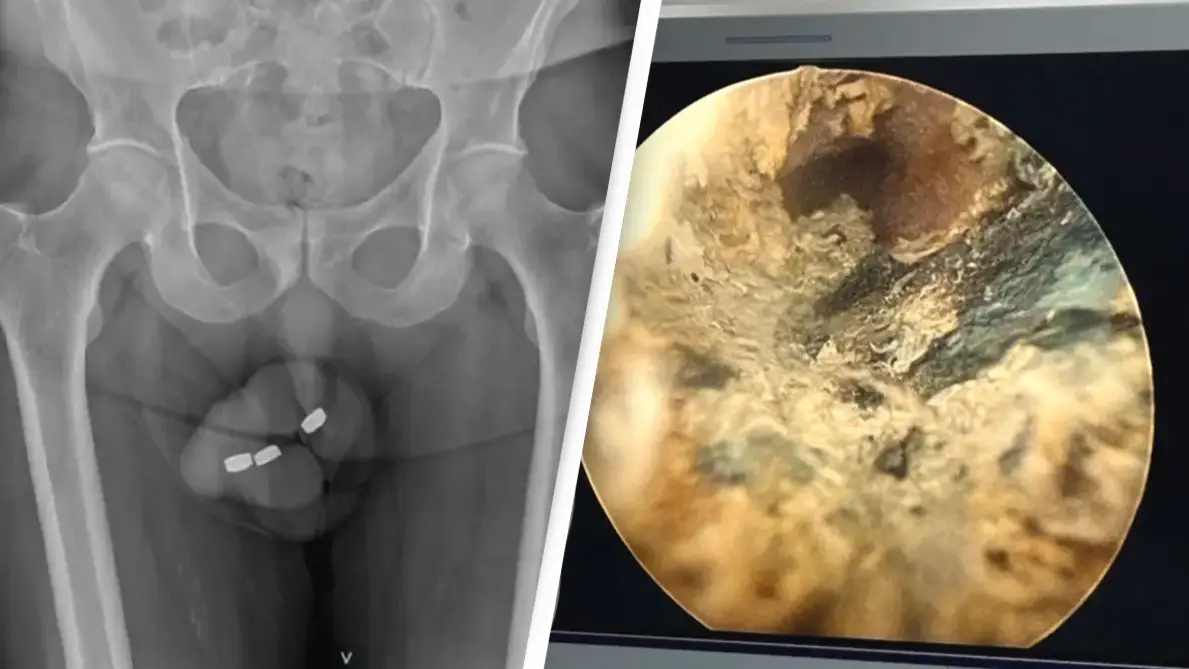

The Australian-born man horrifyingly needed urgent urethra surgery after jamming three button-style batteries into his penis.

During the man's recent episode with batteries, they had 'migrated more proximally within the penile urethra' after a few unsuccessful attempts to remove them.

"All extracted batteries were coated with black tar-like material," the study noted.

The doctors discovered the man developed an 'extensive degree of necrosis' - subsequently meaning part of his urethra had to be removed.